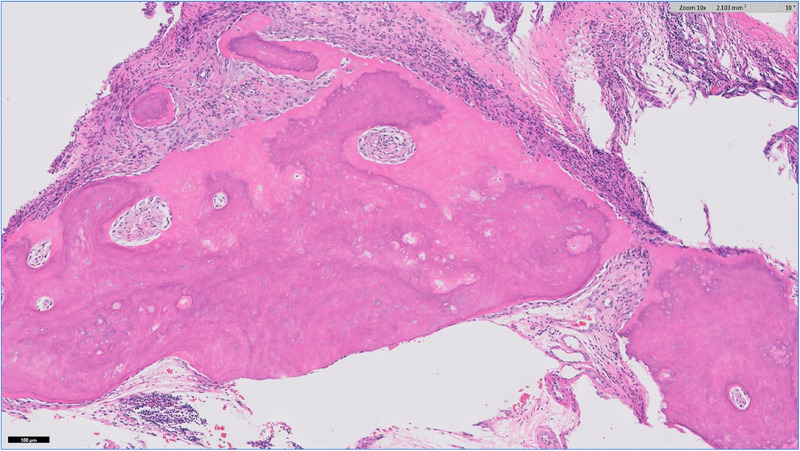

Case summary: A 5-year-old neutered male domestic medium-hair cat was referred to the internal medicine department with upper respiratory signs and limb pain. Computed tomography (CT) revealed diffuse osteosclerosis, showing severe osseous thickening of the nasal turbinates and near-occlusion of the nasal passages. No new or healed fractures were observed. Additional diagnostic tests revealed no infectious or neoplastic causes. The cat was treated supportively for pain and nasal inflammation. One year after the diagnosis, the cat was described as having an acceptable quality of life at home, despite ongoing clinical signs of nasal congestion.

Relevance and novel information: Chronic upper airway congestion is a common presenting complaint in feline patients. This report describes the imaging findings in a cat in which upper airway signs were due in part to systemic bone pathology. Previous reports suggest that the most common causes of chronic nasal congestion are acquired conditions with poor prognosis, such as lymphoplasmacytic rhinitis, neoplasia, or fungal infection. Diseases that cause diffuse osteosclerosis in cats are poorly understood. This report describes a case of diffuse osteosclerosis in a young cat with no other known comorbidities. The clinical picture is similar to descriptions of an osteosclerotic bone disorder in humans commonly referred to as autosomal dominant osteopetrosis type 1. Since no targeted treatments are available to reverse the osseous changes, the patient was treated supportively with pain management and corticosteroids. Recent developments in our understanding and treatment of similar human diseases may guide future advances in veterinary medicine.